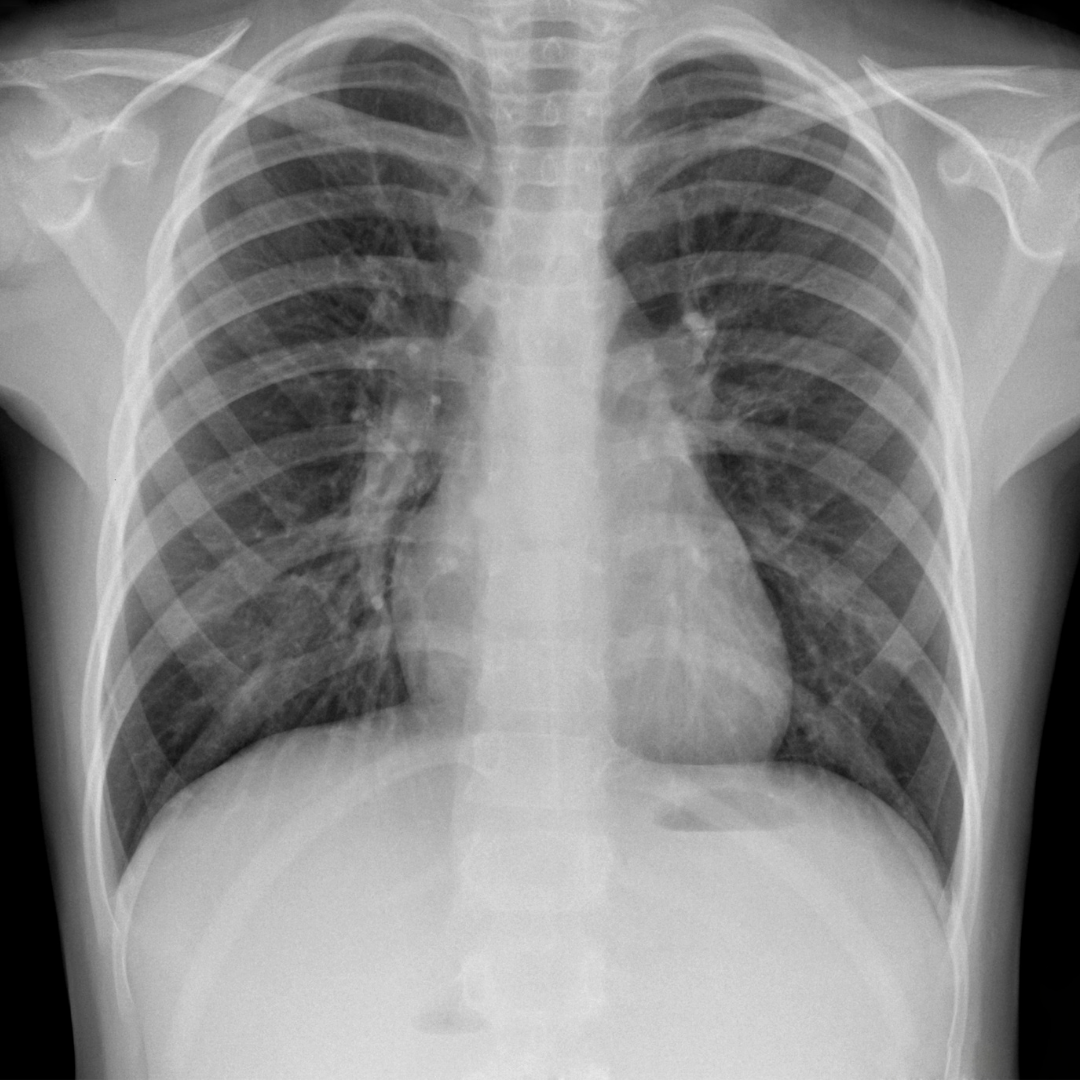

- ILO 2011-D Standartlarında çekilmiş Dijital Göğüs Radyografisi

- ILO 2011-D Standartlarında çekilmiş Dijital Göğüs Radyografisi radyolog değerlendirme raporu

- Çekilen Dijital Göğüs Radyografileri, ILO Pnömokonyoz Radyografileri Uluslararası Sınıflandırması Rehberindeki standartlara uygundur, birinci ya da ikinci teknik kalitede dijital göğüs radyografi çekimi ve görüntülemesi yapılacaktır.

- Çekilen Göğüs Radyografileri, ILO Pnömokonyoz Radyografıleri Uluslararası Sınıflandırması Rehberindeki standartlara uygun olarak en az 21" (inç) büyüklükte medikal ekranda okunup değerlendirilir.

- Çalışanların pnömokonyoz yönünden akciğer radyografilerinin değerlendirilmesi ILO Pnömokonyoz Radyografilerin Uluslararası Sınıflandırması Rehberine göre yapılacaktır. Değerlendirmeler ILO Uluslararası Pnömokonyoz Radyografileri Sınıflandırılması konusunda eğitim almış ve "ILO Pnömokonyoz Okuyucu Sertifikası" sahibi olan 2 (iki} okuyucu tarafından yapılır.

- Okuyucular deneyimli ve kendi alanında uzman olan kişilerden oluşmaktadır. Teklif sırasında okuyucuların sertifika bilgileri paylaşılacaktır

- Okuyucuların her biri radyografilerin değerlendirmesini birbirinden bağımsız olarak, kör okuma şeklinde yapılır.

- Her bir çalışan için "nihai değerlendirme sonuç raporu" düzenlenecek, 2 hekim tarafından da kaşelenip imzalanır.